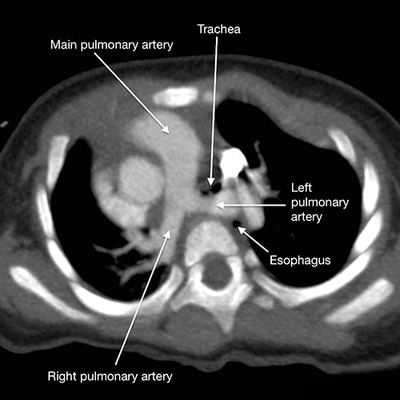

肺动脉吊带是一种罕见的先天性心血管畸形,又名迷走左肺动脉,是左肺动脉异常起源于右肺动脉的后方,呈半环形跨过右主支气管向左穿行于食道前和气管后到达左肺门,常合并气管下段、右主支气管和食管不同程度的压迫。此外,动脉导管或韧带向左后方与降主动脉相连,此结构和异常的左肺动脉一起形成的血管环可压迫左主支气管。

肺动脉吊带是一种罕见的先天性心血管畸形,又名迷走左肺动脉,是左肺动脉异常起源于右肺动脉的后方,呈半环形跨过右主支气管向左穿行于食道前和气管后到达左肺门,常合并气管下段、右主支气管和食管不同程度的压迫。

根据左肺动脉起源情况,肺动脉吊带可分为完全型和部分型。完全型是指左肺动脉主干从右肺动脉发出;部分型是指左肺动脉部分分支从右肺动脉发出,而左肺动脉主干及其他分支起源和走行正常。部分型以左上肺动脉起源异常多见,而左下肺动脉起源异常罕见。

肺动脉吊带患儿气管狭窄的原因除异常走行的左肺动脉压迫气管以及压迫造成的气管软化外,也可能是合并膜状软骨缺失的完全性气管环造成的。